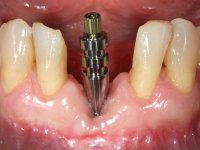

After the CBCT evaluation, our option was to place the dental implant in the central position of the edentulous area for 4 mains reasons:

• Preservation of the bone in the mesial surfaces of the adjacent teeth.

• The thickness (buccal-lingual) was higher in the area.

• Biomechanical, the position was more favourable.

• The esthetic rehabilitation with gum-shade ceramics was easier with the implant placed in this position.